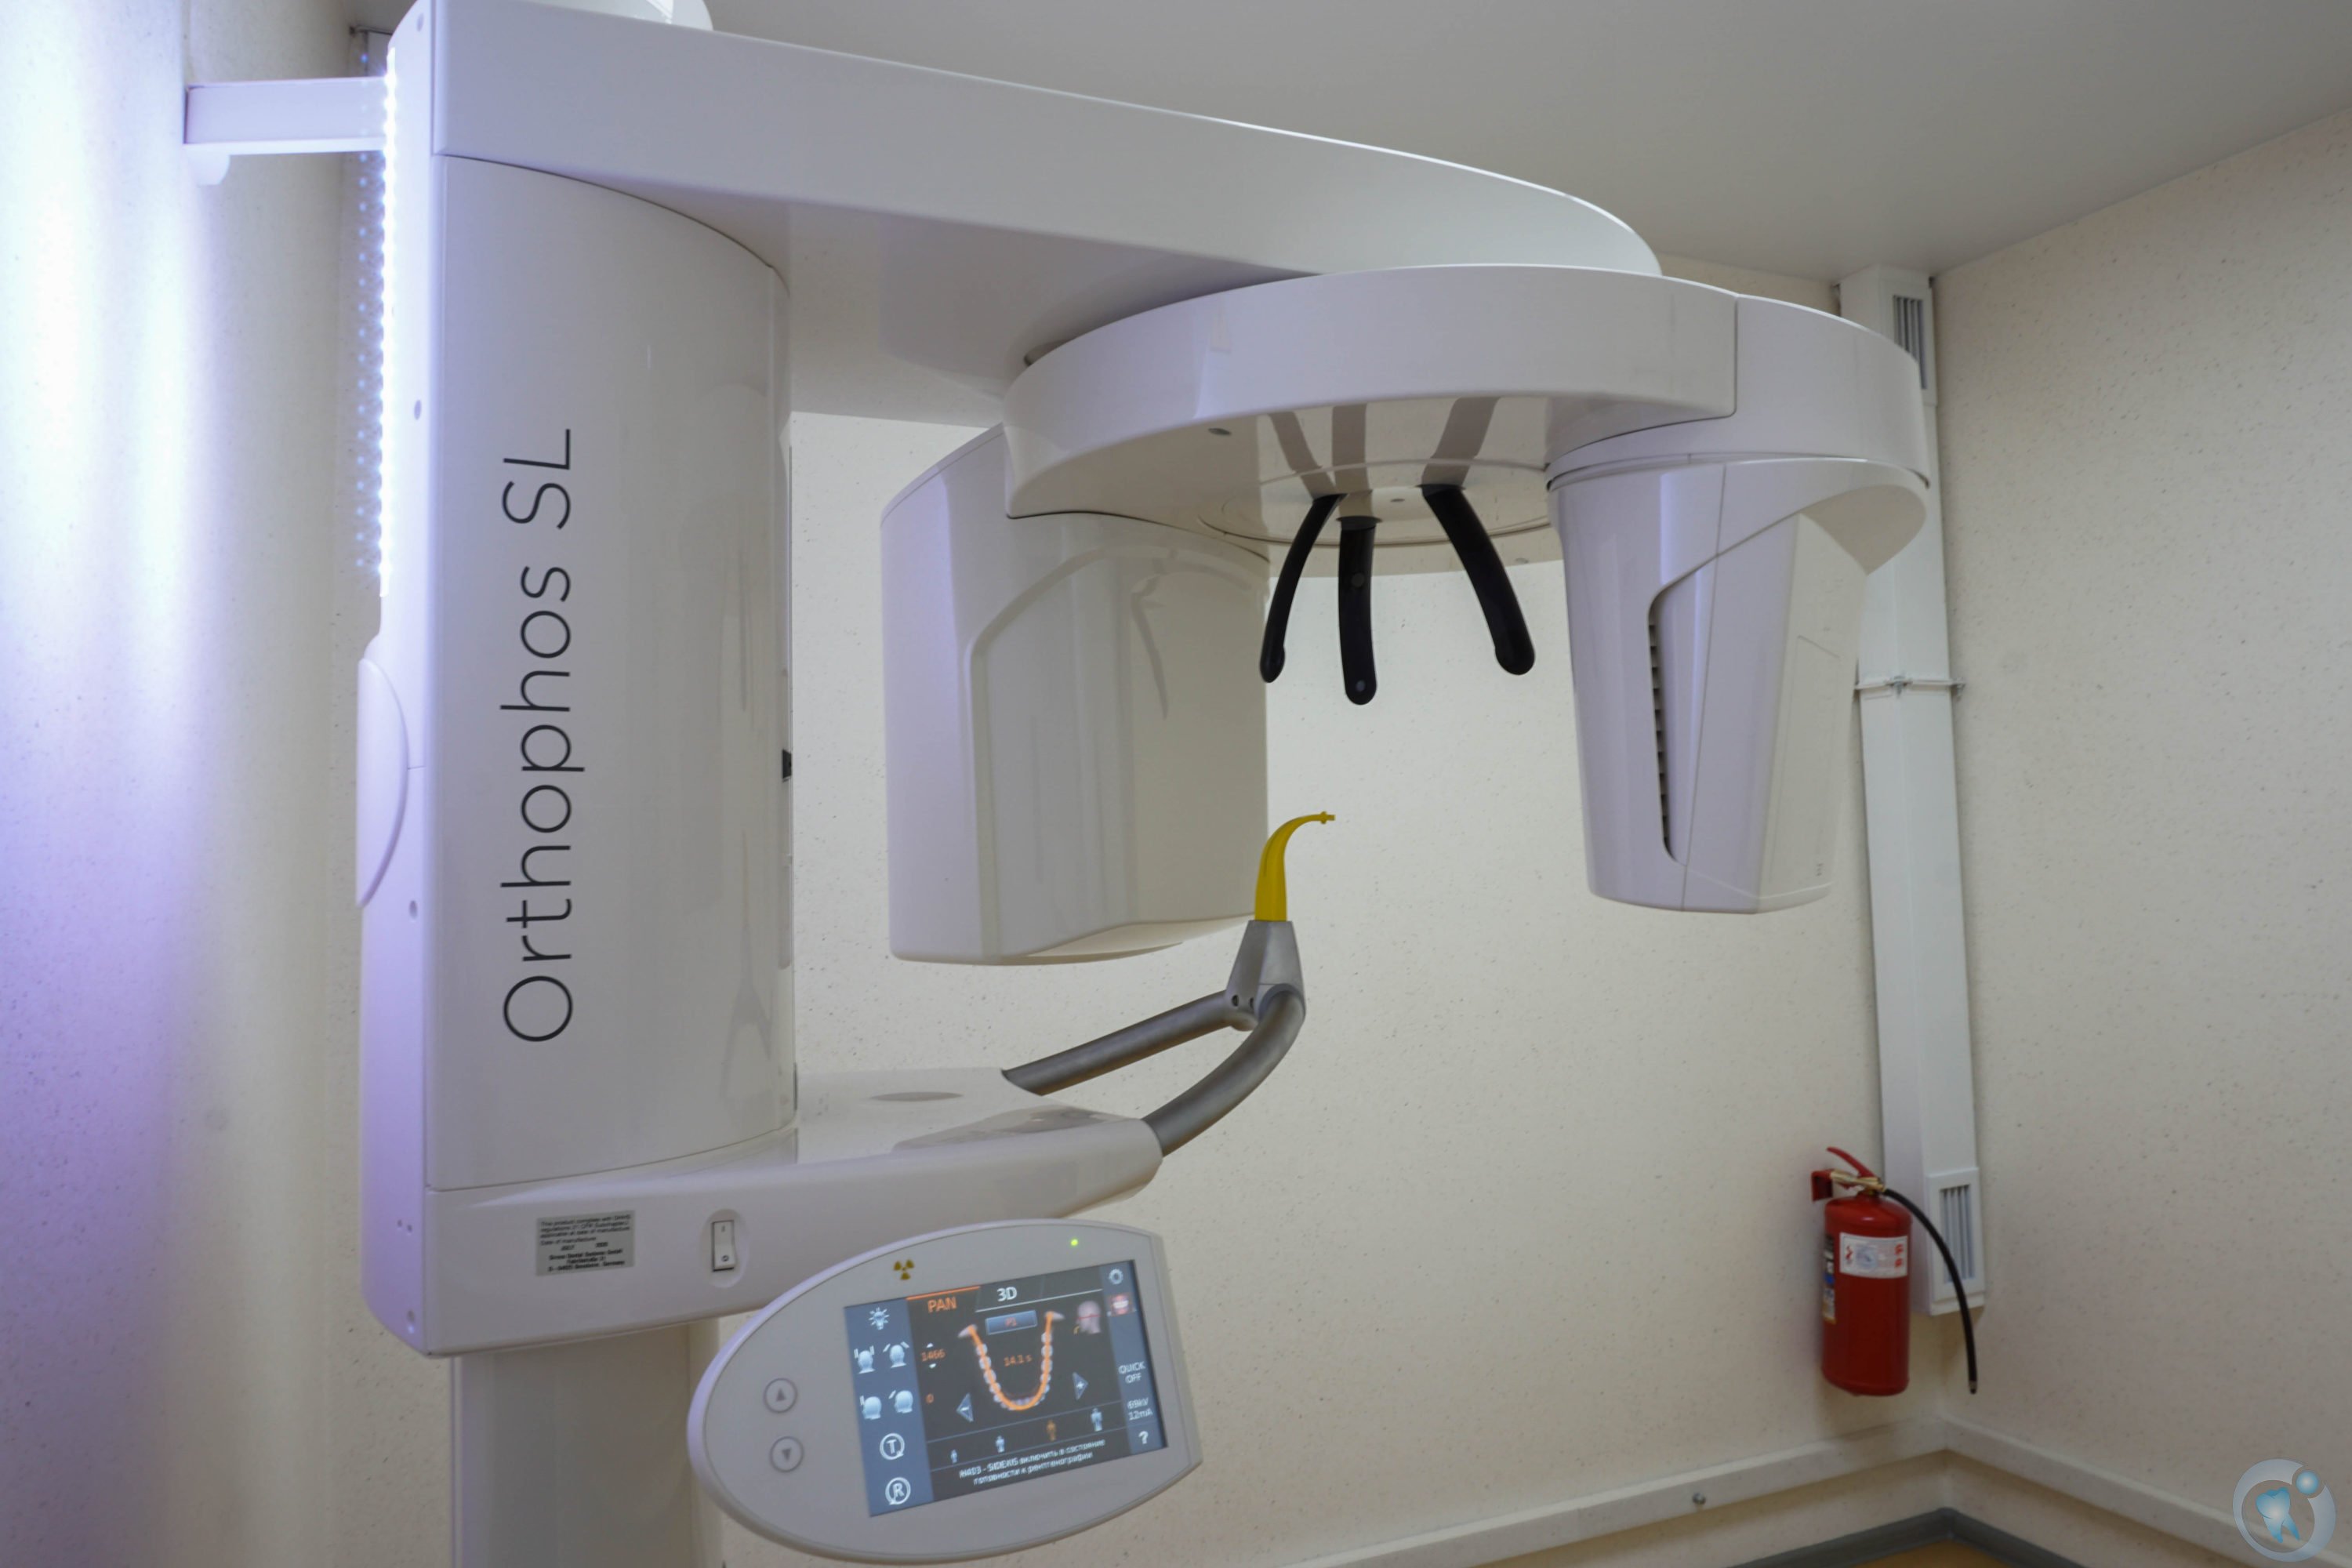

Фотографии и изображения КТ аппарата ORTHOPHOS SL